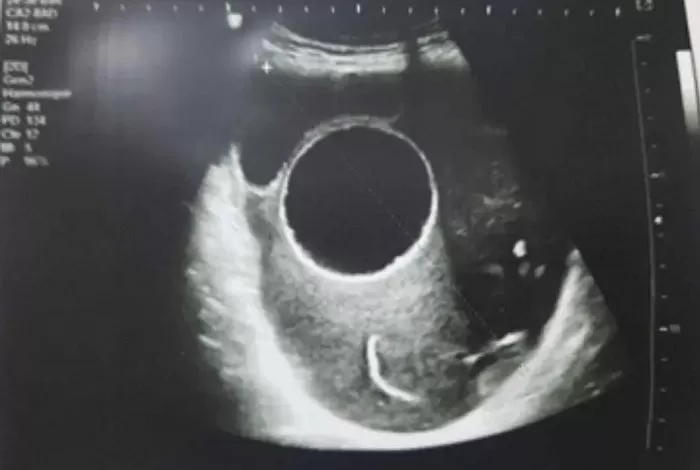

5日(現地時間)、英国の日刊紙デイリーメール(DailyMail)などによると、妊娠20週目だったチュニジアの26歳女性が、骨盤部位にテニスボール2個分の大きさの嚢胞ができ、緊急手術を受けたという「臨床および医療症例報告オープンジャーナル(Open Journal of Clinical and Medical Case Reports)」の事例を報じた。

当時妊娠中だったこの女性は、6か月間続く腹痛で受診した。その際、骨盤から巨大な嚢胞が見つかった。

医療チームは、女性の骨盤に位置する嚢胞が破裂すれば胎児に影響を与える可能性があると判断し、直ちに摘出手術を行った。